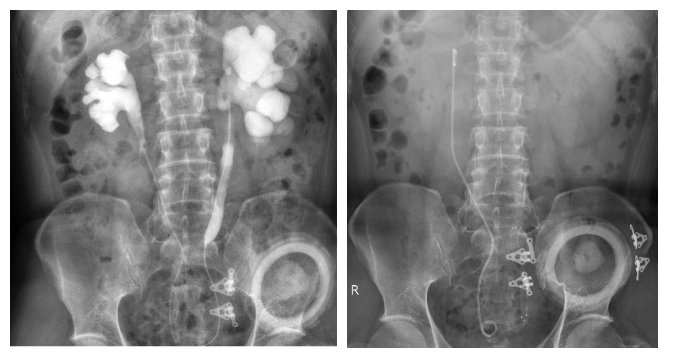

左:术前患者双侧输尿管狭窄,右:术后复查腹部卧位片

近日,马王堆院区首例新型覆膜支架置入术在泌尿四科成功实施,患者通过手术解决了左侧输尿管梗阻、尿液引流不畅的问题,已经顺利康复出院。

充分了解到这种新型覆膜支架的特点后,杨先生表示,“为了不用每年频繁更换输尿管D-J管、更大程度地挽救我的肾功能,不管有什么样的风险,都愿意积极去尝试,因为这已经是多处求医了解到的最好的办法了”。在患者和家属的强烈要求下,经过完善的术前准备,杨科主任团队为杨先生在全麻下成功实施了左侧输尿管狭窄球囊扩张+覆膜支架置入术。由于术中需要C臂机X线反复定位狭窄段和支架的位置,杨科主任医师团队的医生们无惧辐射和辛苦,不断调整、精准定位支架,终于成功扩开了患者左侧输尿管的较长狭窄段。